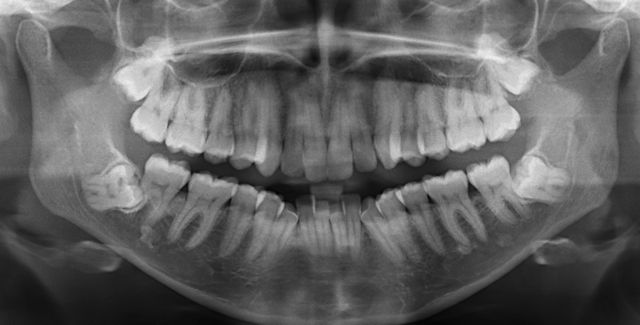

The most common X-Ray required is an OPG, which will show all the wisdom teeth, it will reveal signs of infection or other pathology, it will highlight the relation of the wisdom tooth to the adjacent molars and will show the proximity of the roots of the wisdom tooth to the inferior dental nerve.

Occasionally, a specialist CT scan, called cone beam CT, will be requested, to examine the relationship of the wisdom tooth roots with the nerve in great detail.